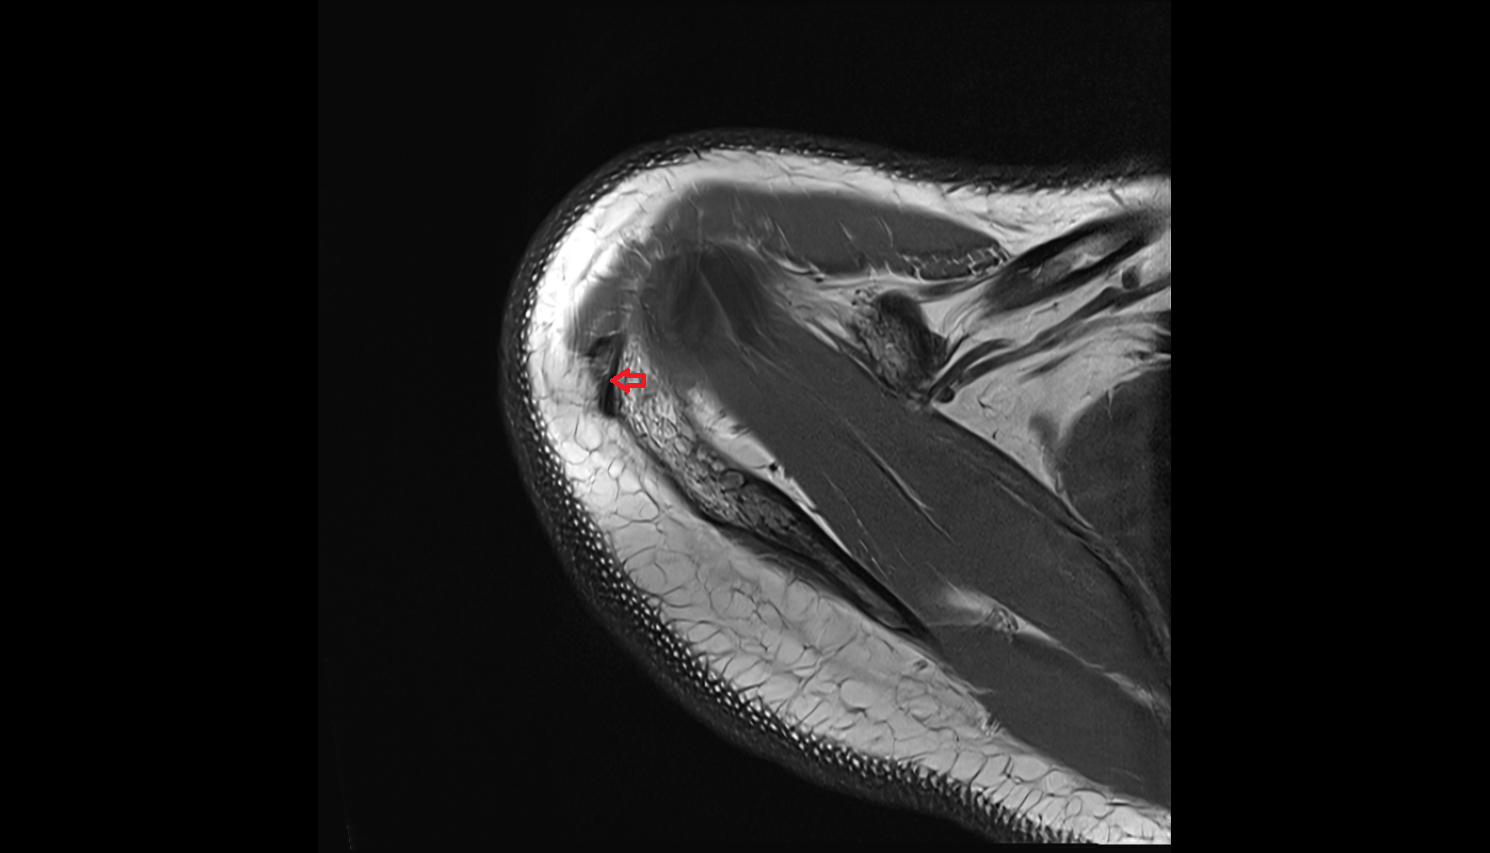

- Temporomandibular joint

- Articular disc of temporomandibular joint

- Articular eminence

- Mandibular condyle

- Mandibular fossa